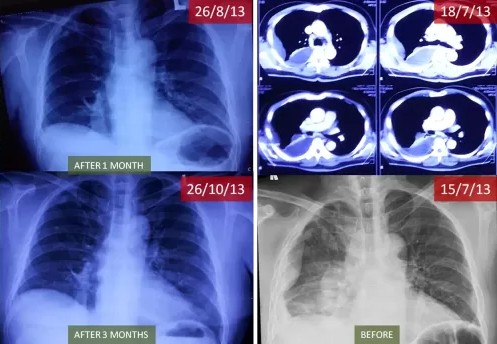

In July 2013, Pak Ichwan was diagnosed with advanced lung cancer that had attached to his ribs and caused fluid buildup, leaving him in severe pain and short of breath. With no viable medical options left, hospital staff advised his family to prepare for the worst and “choose a burial place,” signaling the end of his journey. Refusing to give up, his family discovered ECCT as a final hope. The results were swift; within one month of use, the fluid in his lungs disappeared, and after three months, the tumor mass had deflated into a stable scar. Ten years later, Pak Ichwan remains healthy and has even remarried, living a full life long after his original prognosis expired.